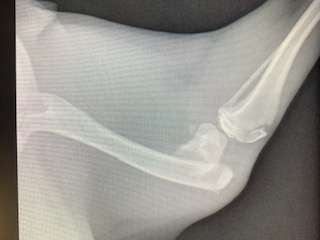

Marigold was found severely injured and was taken to the Humane Society of Parkersburg after being likely hit by a car. At only 8 months old, the diagnosis of a broken femur was devastating, and expensive.

The Humane Society of Parkersburg received an estimate of $2800 to repair her leg, but that is a lot for a shelter to spend on just one animal. They were afraid they would have to choose the option that was within their budget- amputation.

The Humane Society of Parkersburg reached out to Dr. Gandolf, who was able to surgically repair the femur- at a cost they could afford! The Animal Care Hospital of Reynoldsburg generously offered their operating room to help make this possible. This affordable alternative allowed the Humane Society of Parkersburg to save Marigold’s leg!